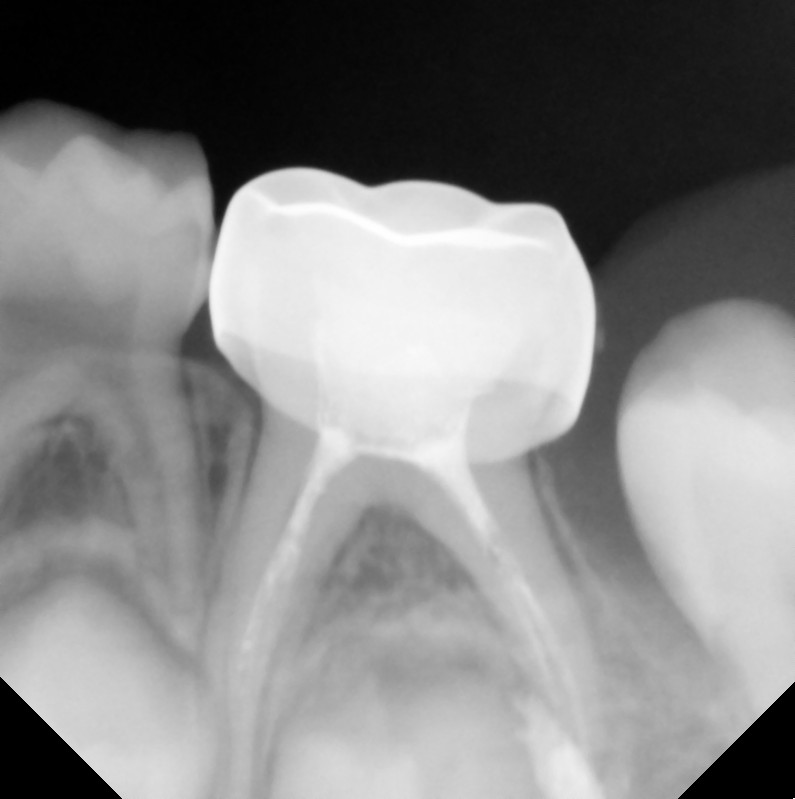

After After

Before Before